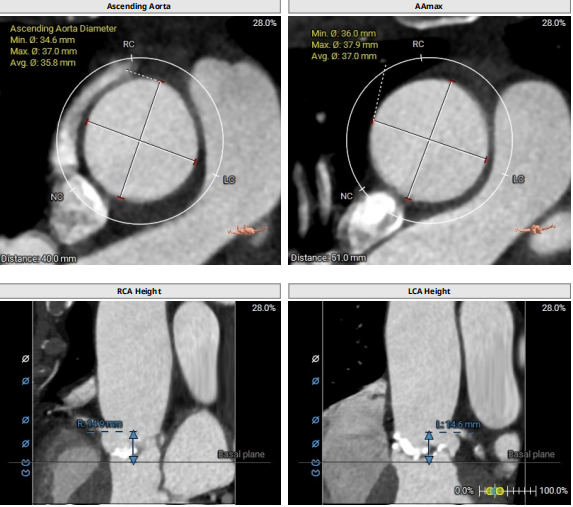

1.该患者为Type-1型二叶瓣。瓣叶略微增厚、重度钙化;

2.钙化主要分布于无冠瓣叶、右冠瓣叶交界,如支架与血管壁贴合不牢,可能会造成较多瓣周漏;

通过充分的术前讨论,翟昌林主任决定使用24mm球囊进行预扩,植入上海微创心通的27# VitaFlow Liberty™瓣膜,使用输送系统自带内联鞘;

患者全麻,气管插管。经左侧股动脉作为辅入路,将6F猪尾巴导管送至无冠窦窦底,右股动脉作为主入路,右侧股动脉作为主入路,置入18F大鞘,先行主动脉根部造影,可见术前有轻中度返流,行24mm球囊进行预扩,无瓣周漏,无明显腰征,双侧冠脉血流通畅,决定按计划选择27# VitaFlow Liberty™瓣膜,在王建安教授的线上指导、刘先宝教授的现场支持下,将瓣膜释放至功能位,再次造影发现瓣膜位置偏高,遂进行回收,再次释放,最终脱钩,再次造影确认瓣膜位置及形态良好,压差从术前的80mmHg降低至2mmHg,无瓣周漏。